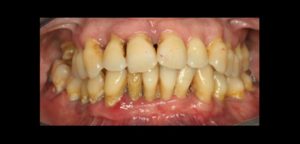

La evaluación correcta de la condición del hueso periodontal es esencial para el diagnóstico, planificación, tratamiento y el pronóstico de la enfermedad periodontal, en conjunto